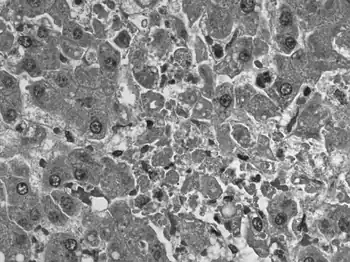

![]() | |

| Negative stain electron micrograph of an arenavirus from a mouse that tested positive for LCM | |